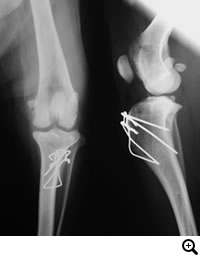

前十字靭帯断裂(小型犬)

症状:後肢の跛行や挙上、突然キャンと鳴いてから後肢をあげる

前十字靭帯断裂とは

膝関節の安定化を担っている前十字靱帯が断裂することにより、膝関節の不安定性が発現します。断裂した前十字靱帯の断端から炎症性のメディエーターが放出されるため、関節炎が起こります。

診断

触診、レントゲン検査、関節鏡検査

治療

関節外制動法(Lateral Suture Stabilization)など。前十字靭帯と同様の働きをする位置に合成靭帯を設置し、膝関節を安定化させる手術法。